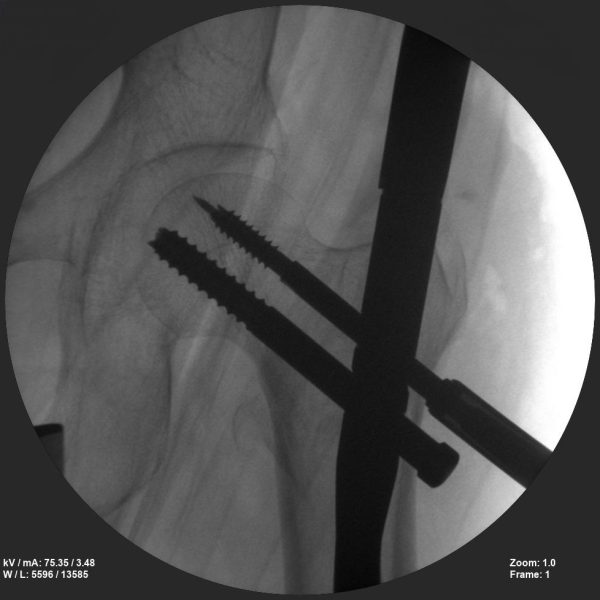

Long bone nailing

Skan-C is a great C-arm for orthopaedic treatments for several reasons